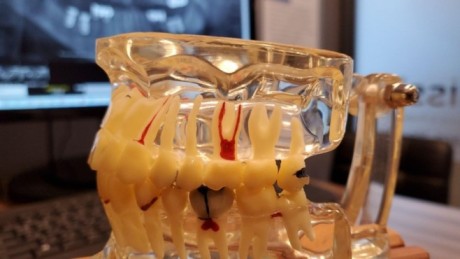

Dental Implant Cost in Chennai 📞 FREE Video Consultation 💬 WhatsApp Instant Quote Dental Implant Cost in Chennai, India – Affordable and Reliable Smile Restoration Chennai has become one of India’s top destinations for dental treatments, especially dental implants, due to its affordable pricing, skilled dentists, and modern clinics. Patients from across India and abroad […]